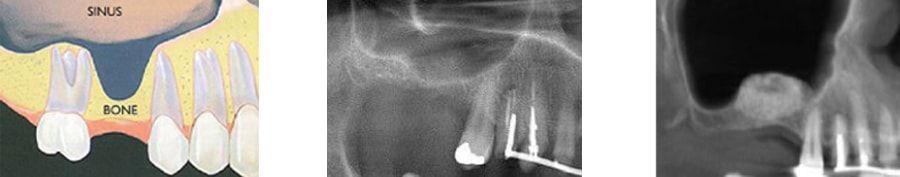

לאחר עקירת שן באזור האחורי של הלסת העליונה, מתרחש תהליך הדרגתי של ספיגת עצם הרכס בלסת. במקביל, ריבוי הנשימות לאורך השנים, נוטה להרחיב את חלל הסינוס ("פנאומטיזציה של הסינוס"). שתי התופעות בו זמנית, מובילות להיעדרות העצם הזמינה להשתלות שיניים, והדבר מחייב את המטופל לשקם את פיו עם תותבת נשלפת.

הניתוח יתבצע ע"י רופא מומחה ומנוסה בכירורגיה עדינה. לפני הניתוח תתבקש למידת המקרה בעזרת צילומים פנורמיים וצילומי סי טי. לרוב, הטיפול יבוצע בהרדמה מקומית וללא אשפוז. מטופל החרד מטיפולי שיניים, יוכל במידת הצורך, לעבור טיפול זה בסדציה עמוקה (טשטוש).

במידה ובסיס רצפת הסינוס המקורי (לפני השתלת העצם ), מספיק עבה (כלומר מעל 3-4 מ"מ), יותקנו השתלים יחד עם הרמת הסינוס, כך שייקלטו בו זמנית השתלים ושתל העצם. במקרים אחרים כאשר רצפת סינוס דקה במיוחד, התקנת השתלים תדחה לשישה חודשים לאחר ריפוי וקליטת העצם. הטיפול המשולב (הרמת סינוס ושתלים), בהחלט מקצר את תהליך שיקום האזור, אך ההחלטה על מהלך הניתוח, נשארת בידיו של המנתח.